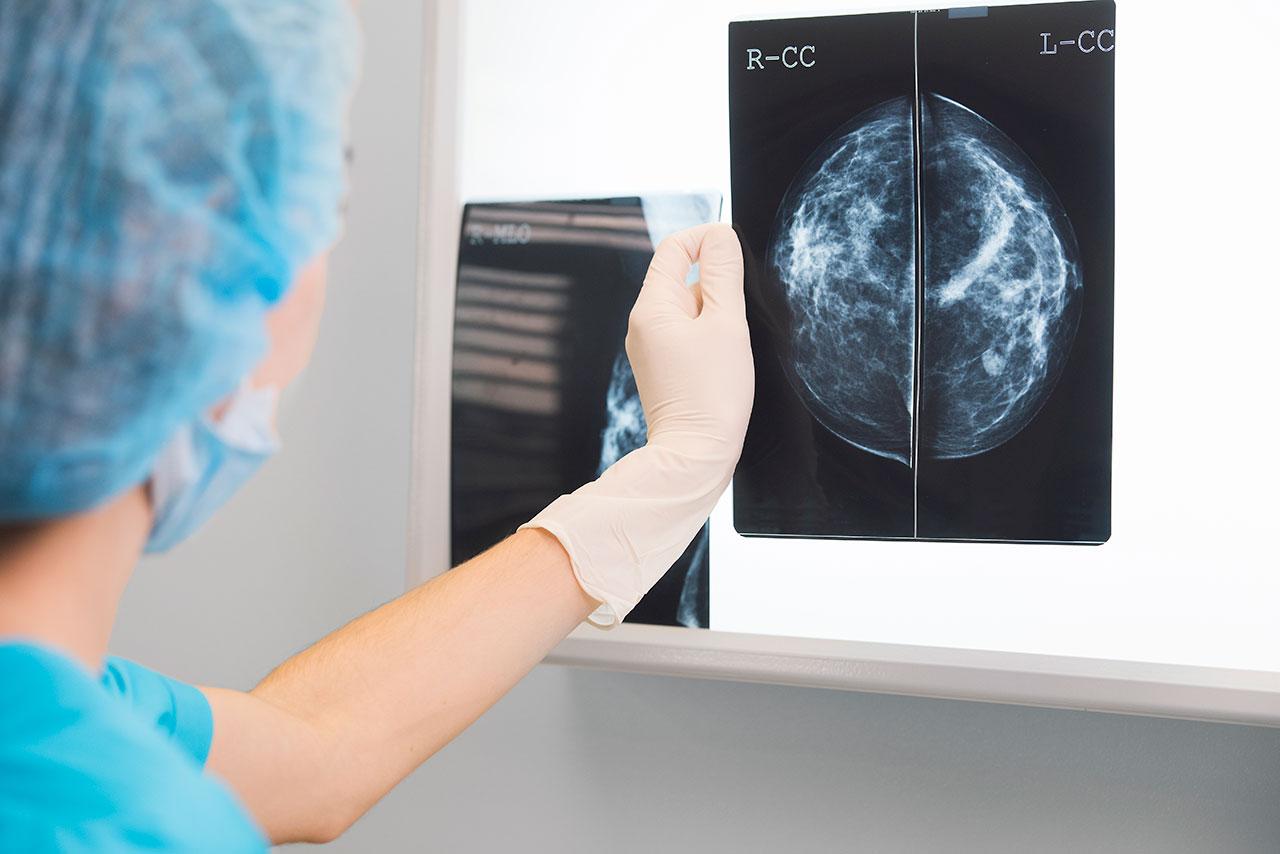

แมมโมแกรม คืออะไร?

“แมมโมแกรม” เป็นการเอกซเรย์เฉพาะเต้านมด้วยเครื่องเอกซเรย์ที่ออกแบบมาโดยเฉพาะสามารถแสดงส่วนประกอบต่างๆ ของเต้านม ได้แก่ เนื้อเต้านม (ซึ่งประกอบไปด้วยท่อน้ำนมและต่อมน้ำนม) ไขมัน ต่อมน้ำเหลืองบริเวณใต้รักแร้บางส่วน และบางส่วนของกล้ามเนื้อทรวงอกที่รองรับเต้านม โดยมีจุดประสงค์เพื่อตรวจหามะเร็งเต้านมในระยะเริ่มแรกตั้งแต่ยังไม่ปรากฏอาการ ซึ่งหินปูนเล็กๆ บางชนิดก็เป็นสิ่งตรวจพบรูปแบบหนึ่งของมะเร็งเต้านมระยะเริ่มแรก โดยหินปูนเหล่านี้จะสามารถตรวจพบได้จากแมมโมแกรมเท่านั้น นอกจากนี้แมมโมแกรมยังสามารถช่วยตรวจหาความผิดปกติอื่นๆ ในเต้านมรวมทั้งช่วยให้การวินิจฉัยแยกโรคของความผิดปกติต่างๆ เหล่านั้นอีกด้วย